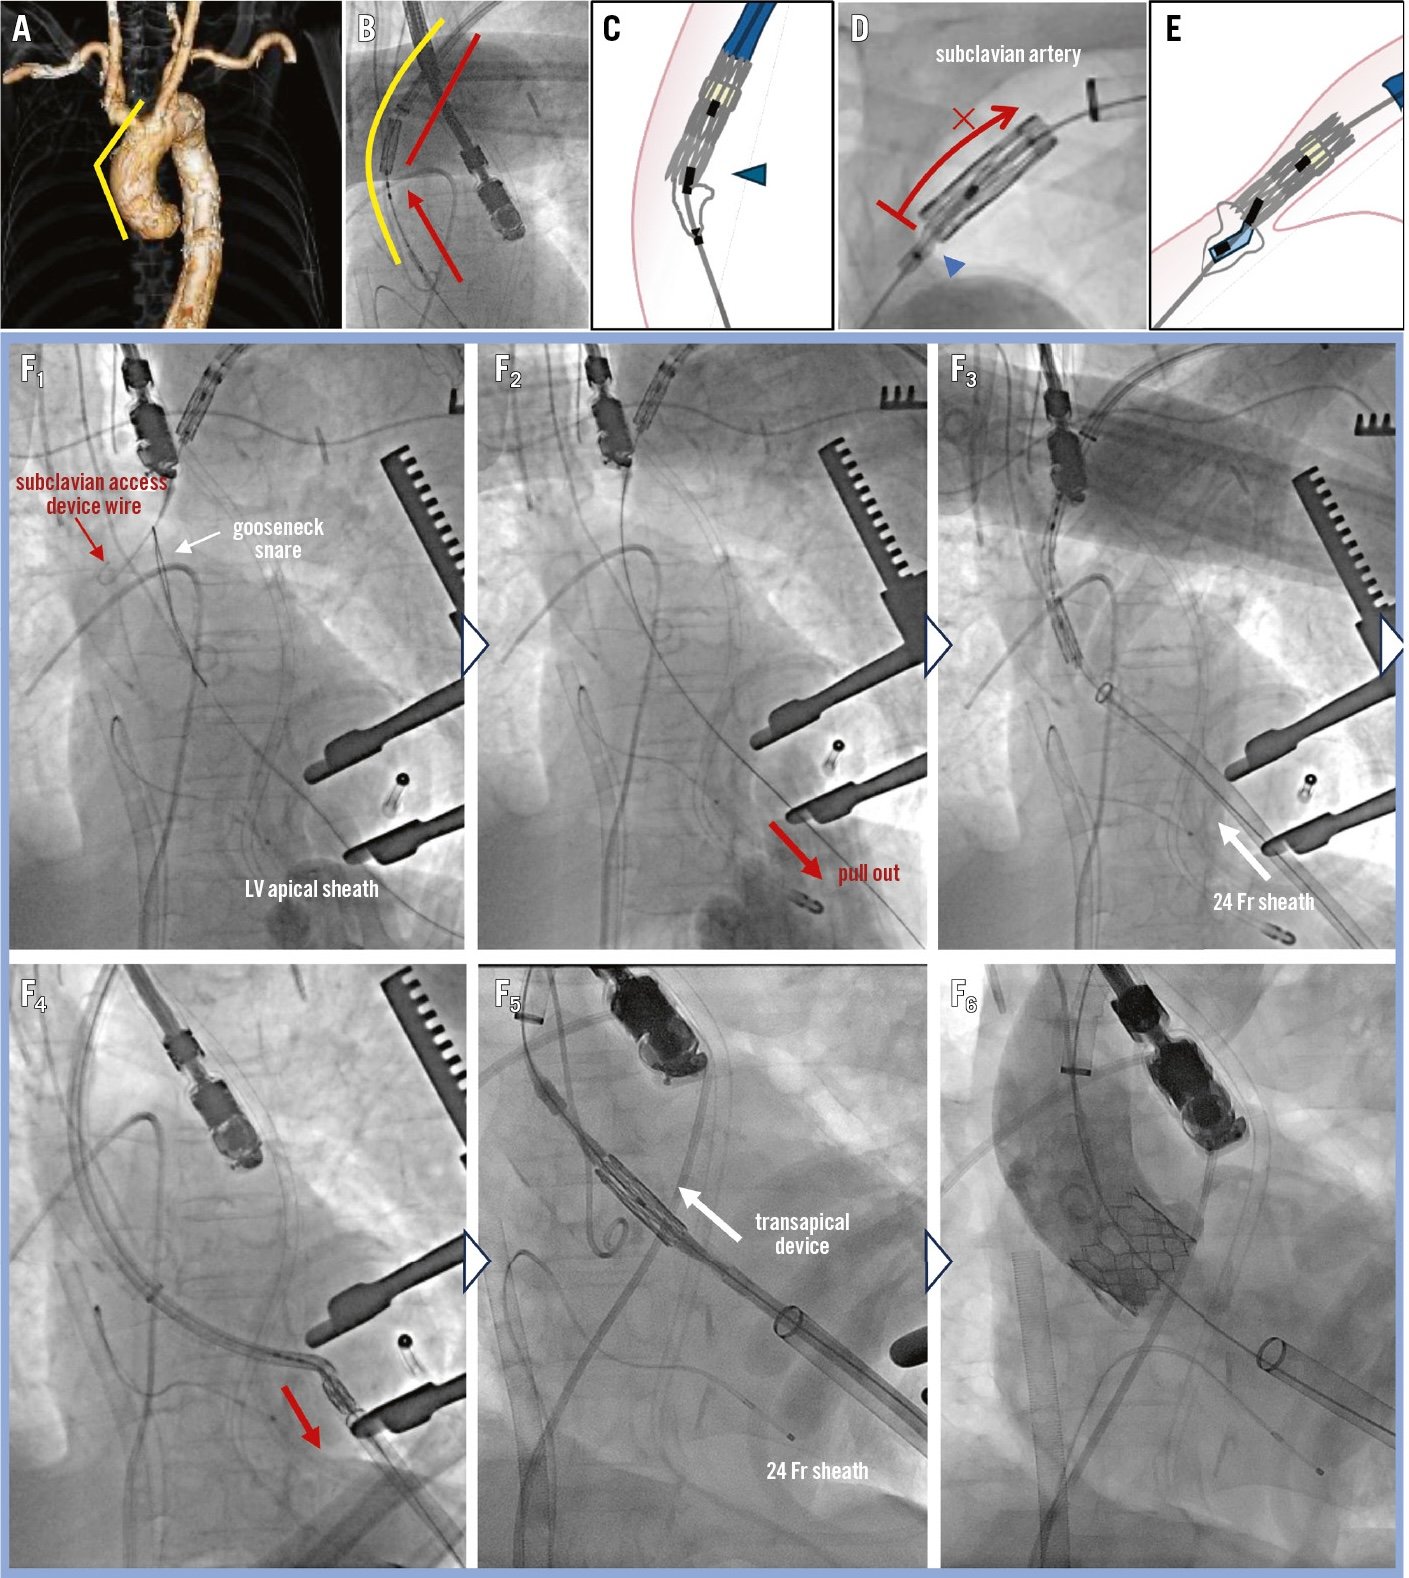

Retrieval of a stuck TAVI device

A stuck transcatheter aortic valve device was successfully retrieved via the left ventricular apex, and a new valve was then implanted using the transapical approach after the complication.